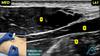

Essa janela é de um bloqueio de membro inferior para cirurgia no tornozelo. O que são as estruturas em destaque?

A

1 - artéria poplíta;

2 - nervo tibial;

3 - veia poplítea

Esse é o bloqueio do nervo ciático na fossa poplítea.